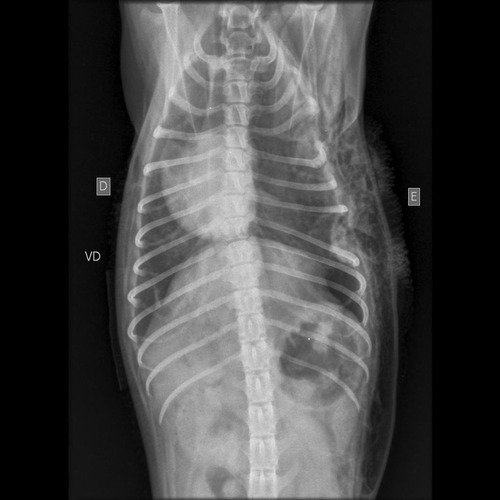

Meu nome é Michele, e essa pequenininha da foto é a belinha um pintcher 0, infelizmente sofreu um ataque de Rottweiler, quebrou 4 costelinhas e perfurou o pulmão, precisa de cirurgia urgente, além das medicações que nem estou contando nesse valor…. não temos esse dinheiro nem mesmo em cartão de crédito mas não queremos desistir da nossa pequena…Agradeço a colaboração de todos cada real ajuda, que Deus retribua em dobro!! Se quiser mais informações pode entrar em contato com o número (12)99687-2640.